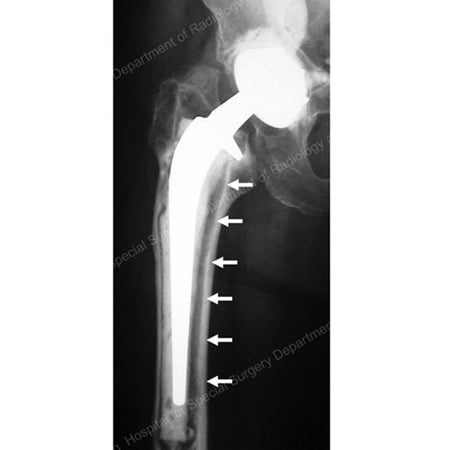

X-ray image showing loose total hip replacement prosthesis.

X-ray of a loose total hip replacement prosthesis showing separation of the stem from the bone (as detailed by arrows)

A loose component can move against the surrounding bone, compounding the bone loss. If the bone loss is severe enough, a spontaneous bone fracture can occur (known as a pathologic fracture).